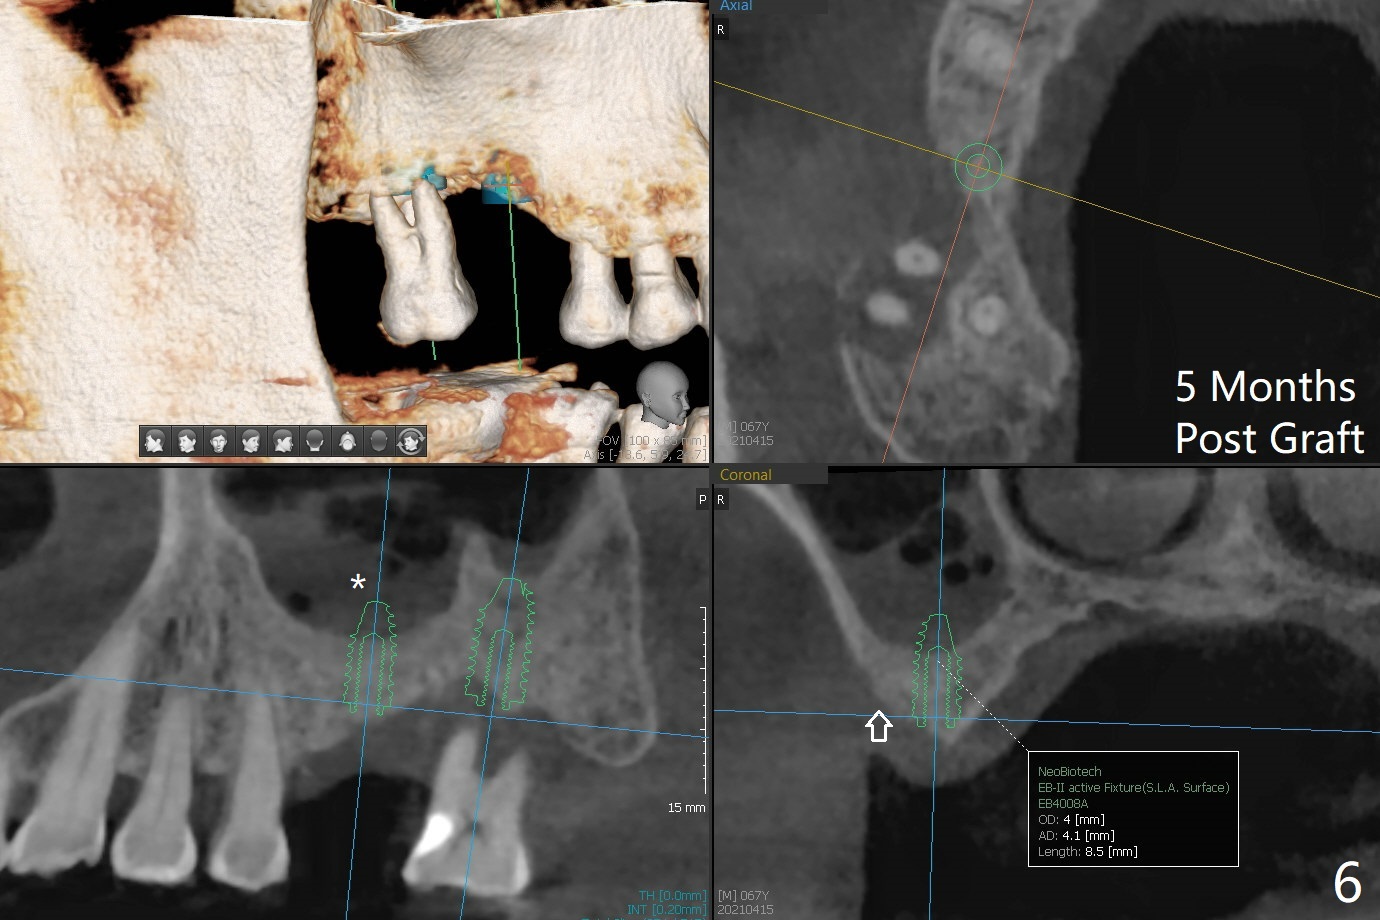

使用来自钻头的自体骨做提升,植体植入后,颊侧骨板薄,刚好骨下。使用5.5毫米profile drill后,放置愈合基台,术后三个月脱落,他再次要求修复,甚至提出退款,不愿意回诊所,因为他有糖尿病,新冠病毒高危人群。 放置小号愈合基台(图二)。他原来托牙是Valplast,没有occlusal rests,不能经过修改临时使用,可能将直接放置修复基台做临时牙冠。放置修复基台后(图三(术后三个月)),制作临时牙冠时,发现前者有些松动,后者就没有粘固。当基台完全就位,它最冠方与植体没有间隙(箭头),根方有间隙(空心箭头)。其实愈合基台也是一样(图一,二)。后来植体松动(术后4个月),拔除,植骨(图四),颊侧骨板缺失(图五:B)。植骨后5个月2号牙疼痛需要拔除种植(图七),与3号牙一起种植(图六),颊侧骨板修复,但是高度有所下降(箭头)。The narrow ridge with the intact buccal plate (Fig.8 >) can hold a 4x8.5 mm implant. The buccal plate is lost 4 months postop (Fig.9) and restores 5 months post graft (Fig.10). Return to Upper Molar Immediate Implant, No Deviation Coronal and Apical Gap in IBS implant Protect Graft Xin Wei, DDS, PhD, MS 1st edition 06/22/2020, last revision 05/02/2021